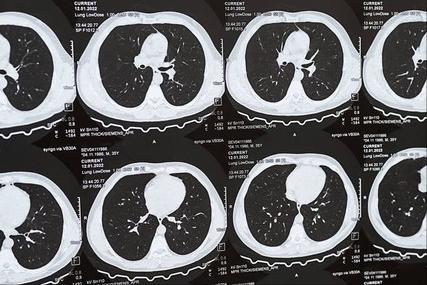

薄层CT、增强CT、PET-CT,肺结节复查做哪个?教授:少花冤枉钱!

薄层CT是肺结节复查的首选方法。它具有高空间分辨率和成像快捷的优势,能够清晰显示肺结节的特征。根据中国肺部结节分类、诊断与治疗指南(2016年版),建议采用螺旋CT容积扫描技术,管电压100 KVp,管电流<40 mAs,总辐射暴露剂量≤5 mSv。扫描后原始数据行薄层重建,重建层厚为0.625 mm-1.25 mm。

此外,定期随访对于肺结节患者至关重要。周贤梅教授强调,肺结节复查多数是对良性病灶而言的,关键在于动态观察。一般发现肺结节,需要进行薄层CT或薄层高分辨CT扫描,以便更好地显示肺结节的特征,并与既往历史影像学资料进行对比。